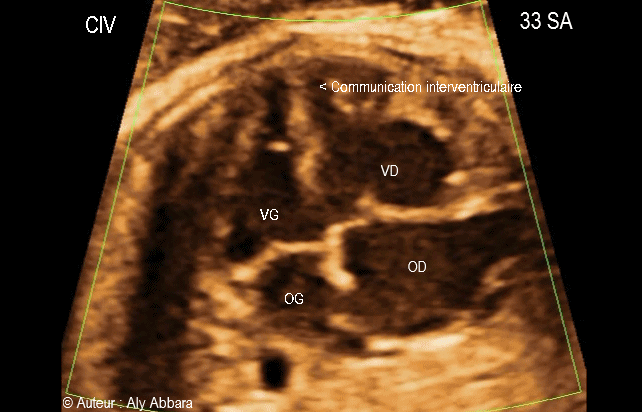

Vidéo et image animée échographiques cardiaques avec Doppler-couleur montrant une malformation cardiaque congénitale isolée ; il s'agit d'une communication interventriculaire (CIV) musculaire, trabéculée et apicale.

Cette CIV musculaire apicale est de moins de 3 mm de largeur, située à l'extrême pointe de ventricule gauche, isolée, sans autre anomalie morphologique ou fonctionnelle cardiaque décelée lors de cette examen.

Le Doppler couleur montre un flux sanguin bidirectionnel sur cette communication interventriculaire apicale.

Fœtus âgé de 33 SA.

On voit bien une CIV musculaire apicale de moins de 3 mm à l'extrême pointe de ventricule gauche.